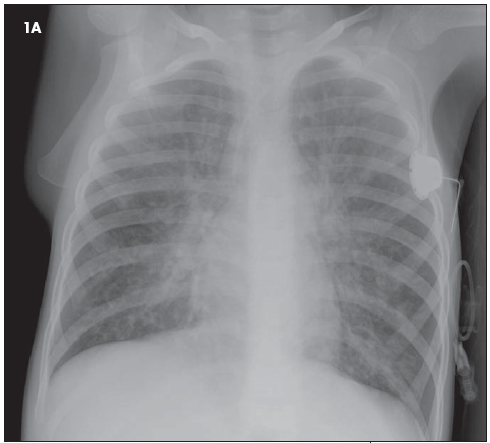

The chest radiographs (Figure 1) of a 9-year-old child reflect the classic findings of a particular disease. Among other findings, the size of the patient's heart is_____?